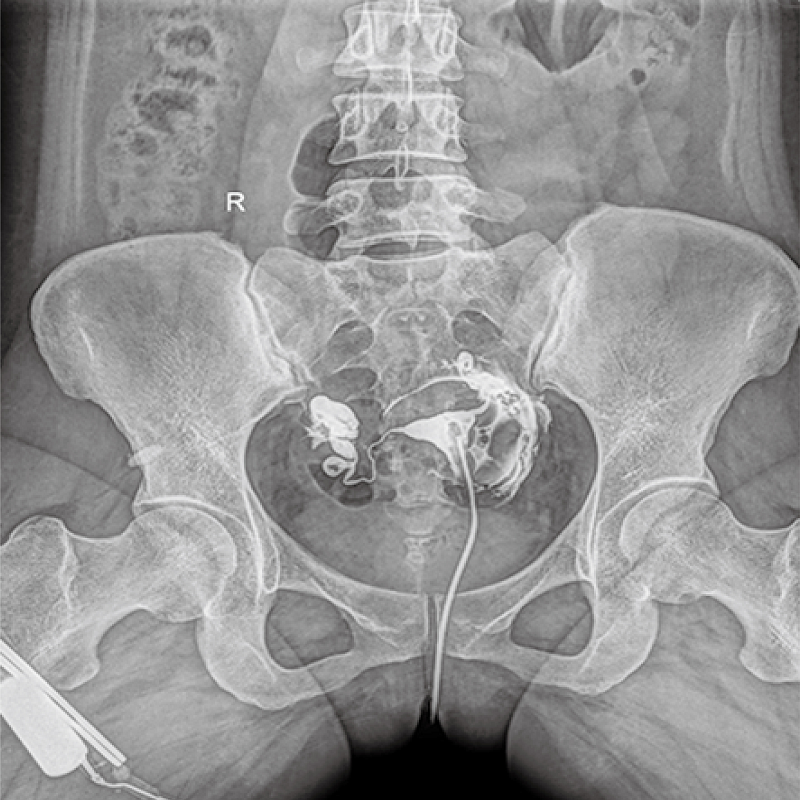

多功能、全視角、真視界,全面突破傳統(tǒng)X線攝影透視理念,通過(guò)一塊新型動(dòng)態(tài)平板探測(cè)器,在檢查中既可實(shí)現(xiàn)數(shù)字透視又可實(shí)現(xiàn)數(shù)字?jǐn)z影,還可做數(shù)字胃腸及數(shù)字造影檢查。

● 只需一塊動(dòng)態(tài)平板探測(cè)器,高效輕松實(shí)現(xiàn)攝影、透視和造影功能,幾乎可以滿足醫(yī)院全科室

●呈現(xiàn)全下肢或全脊柱圖像

●在脊柱及下肢畸形矯正手術(shù)治療中,為術(shù)前方案制定和術(shù)后復(fù)查提供精準(zhǔn)測(cè)量

●有效解決傳統(tǒng)X光片不能一次成像問(wèn)題,為患者提供更加優(yōu)質(zhì)的醫(yī)療服務(wù)

點(diǎn)片裝置可實(shí)現(xiàn)大范圍縱向移動(dòng),高效完成各部位、全身拼接等檢查需求